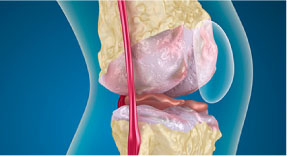

Wear porc - a fő oka a betegségek az ízületek (artritisz, artritisz, synovitis, osteochondrosis, stb ...). Vékony, száraz porc nem képes megvédeni az ízületi felületeket és a közös bomlani kezd, és deformálódhat. Ízületi betegség önmagában nem halad. A következmény gondatlan magatartása és kezelés hiánya vezet a progresszió izületroncsolódás.

Helyreállítani az ízületi porcok porcsejtek szükséges - építőelemek porcszövet. Folyamatosan „leszerelt”, és újjáépíteni a porc. A folyamat lassú és bonyolult. Ez néhány hónapig tart. Hatékonysága függ a kedvező feltételeket teremtett. Először el kell távolítani a gyulladásos folyamatot, majd - annak biztosítása érdekében, a porc szerkezeti elemek.

Kék vonal „Arthro AKTIV” megteremti a legjobb feltételeket a fejlődés porcsejtek porc frissítéseket. Boswellia kivonat (tömjén) - blokkolja a celluláris faktorok képződéséért felelős anyagok, amelyek növelik a gyulladást. Basic hondroprotektory (kondroitin és glükózamin) csökken porc felülete a közös: megnövekedett „konstrukció” aktivitás kondrocita összetétel és javítja a kenési tulajdonságai szinoviális folyadék. a kollagén-hidrolizátum biztosít ereje és rugalmassága porcok és szalagok.